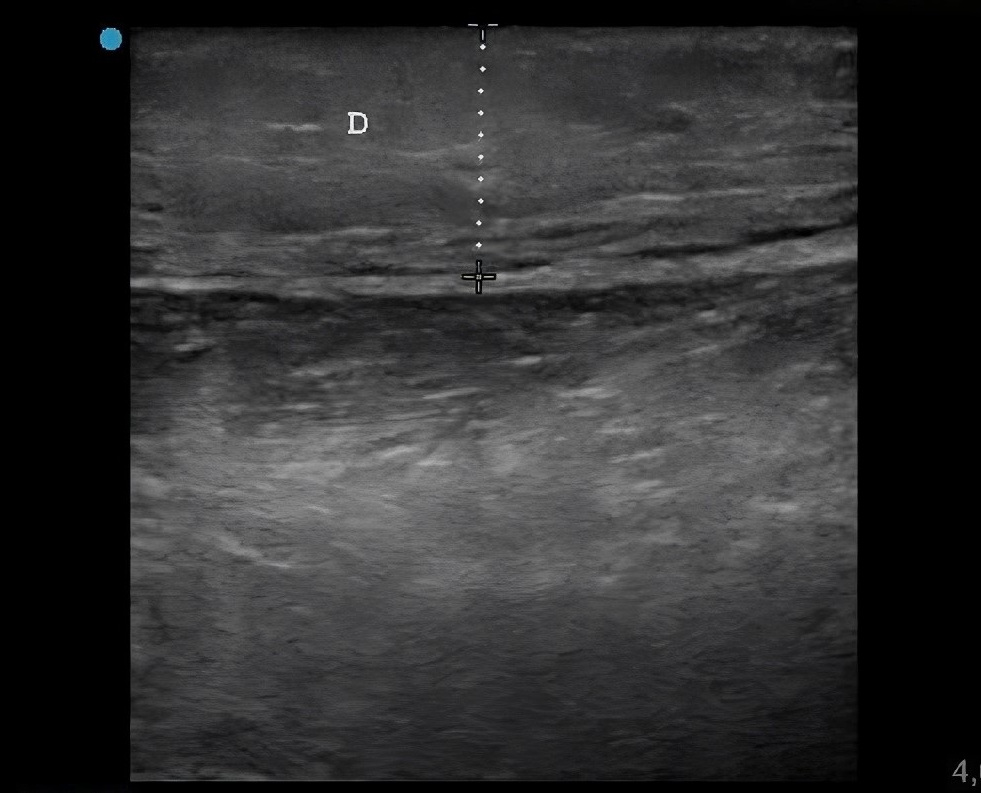

Niño de 7 años que consulta en Urgencias por edema y eritema en la región lateral del tercio distal del miembro inferior derecho tras la picadura de un insecto de 48 horas de evolución. Se encuentra afebril. En la exploración destacan: aumento de temperatura, eritema y edema importante de la piel que rodea la puerta de entrada, que alcanza hasta el dorso del pie derecho, sin limitación a la movilización. En la analítica sanguínea no existe elevación de reactantes de fase aguda ni de creatina quinasa. Se realiza ecografía a pie de cama de partes blandas y se encuentran los hallazgos de las imágenes (Figuras 1 y 2).

Figura 1. Ecografía musculoesquelética y de partes blandas de la región lateral del tercio distal del miembro inferior derecho. Se visualiza aumento de ecogenicidad y grosor (13,2 mm) del tejido celular subcutáneo (delimitado por la línea de puntos blancos) con pérdida de la diferenciación con la dermis.